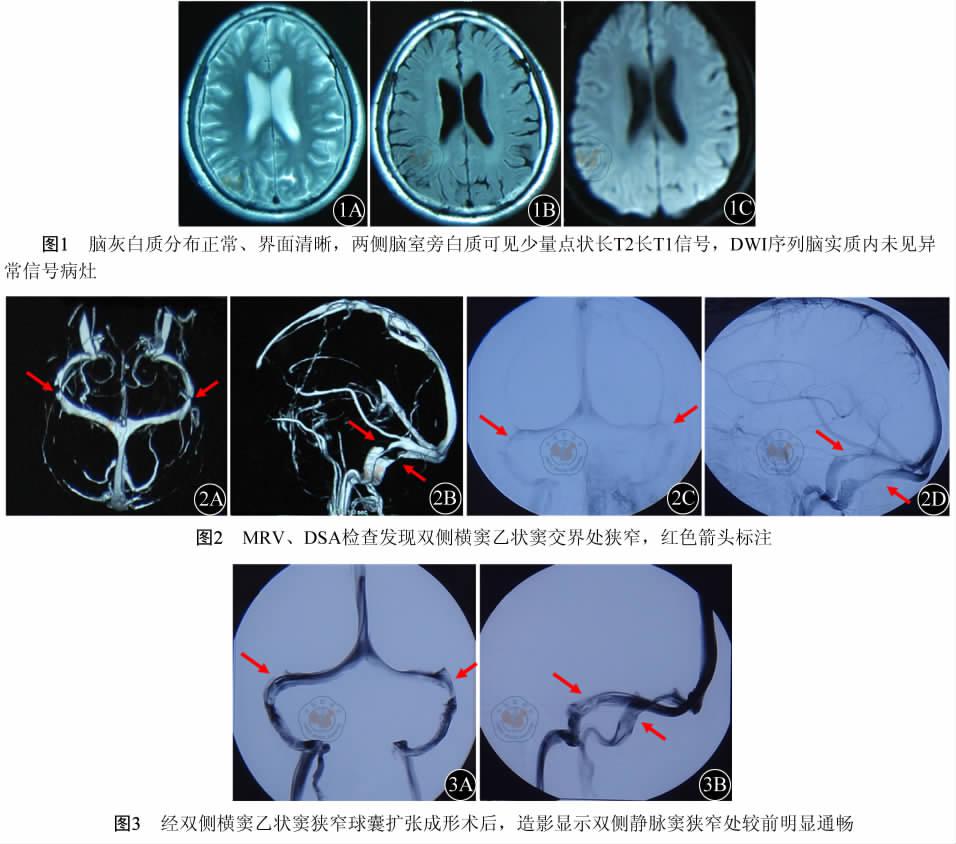

颅内静脉窦狭窄致29岁青年失明,支架植入术改善静脉回流,解除高颅压!

良性颅高压综合征与静脉窦狭窄